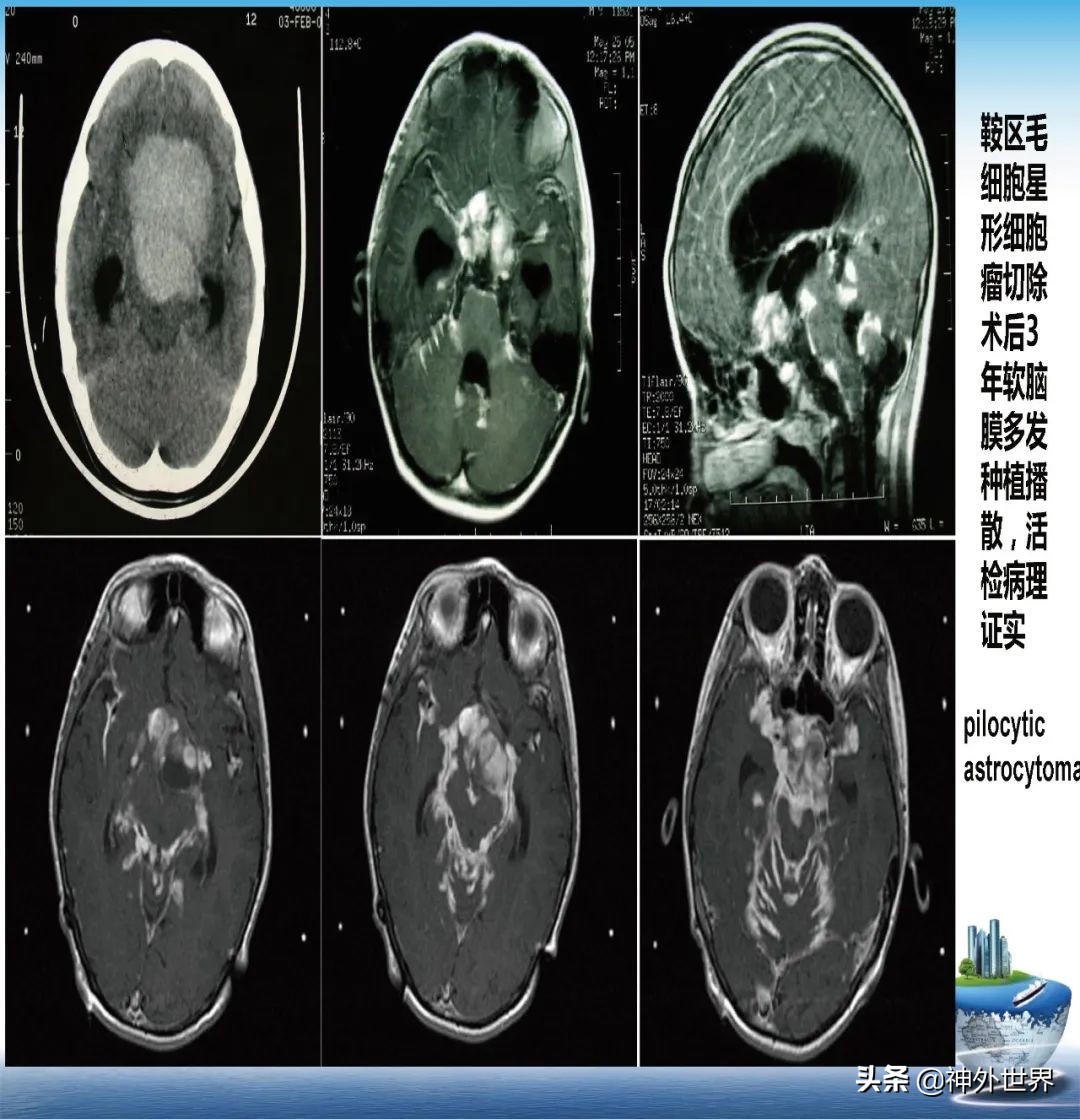

专业方向:颅内肿瘤的显微外科手术切除,颅咽管瘤综合治疗具有特色;在立体定向脑内病灶活检、立体定向清除脑干血肿、立体定向间质内放疗、机器人辅助神经外科手术方面具有专长。